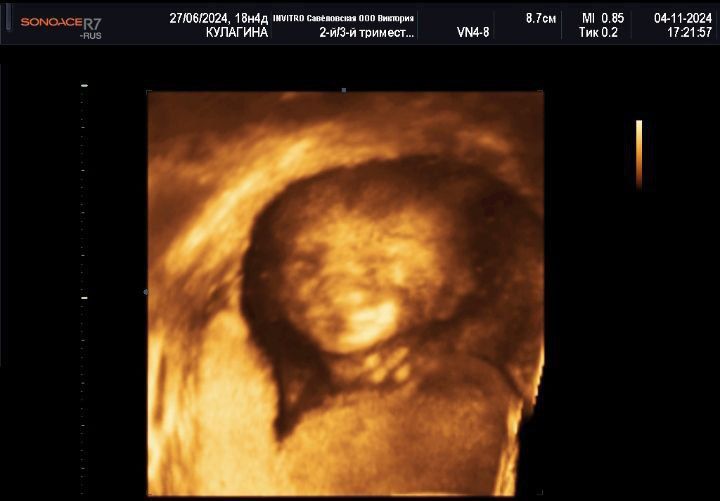

Держите фотографию нашего принца! Люблю и жду тебя, мой мальчик!

Трудно поверить, но за день до этого меня накрыло, что у нас будет не девочка. Я очень рада, что ребеночек здоровый, но ехала и ревела, что не будет розовых одежд, бантиков и прочего. Боже, как стыдно сейчас читать! Вчера поехали на 3 д узи, чтобы посмотреть на малыша и убедиться, что ошибки нет, там мальчик. И он с первых секунд начал показывать свое хозяйство)). И тут пришло осознание - эй, ты чего, это ТВОЙ малыш!!!! Посмотри, какой он прекрасный, здоровый, очаровательный и милый! Да он лучшее, что могло со мной случиться! Может, гормоны так кроют, но я до сих пор готова разреветься от счастья! Узистка еще сказала, что он прям фотомодель, так и позировал, что меня еще больше умилило, потому что мое хобби связано с моделингом)